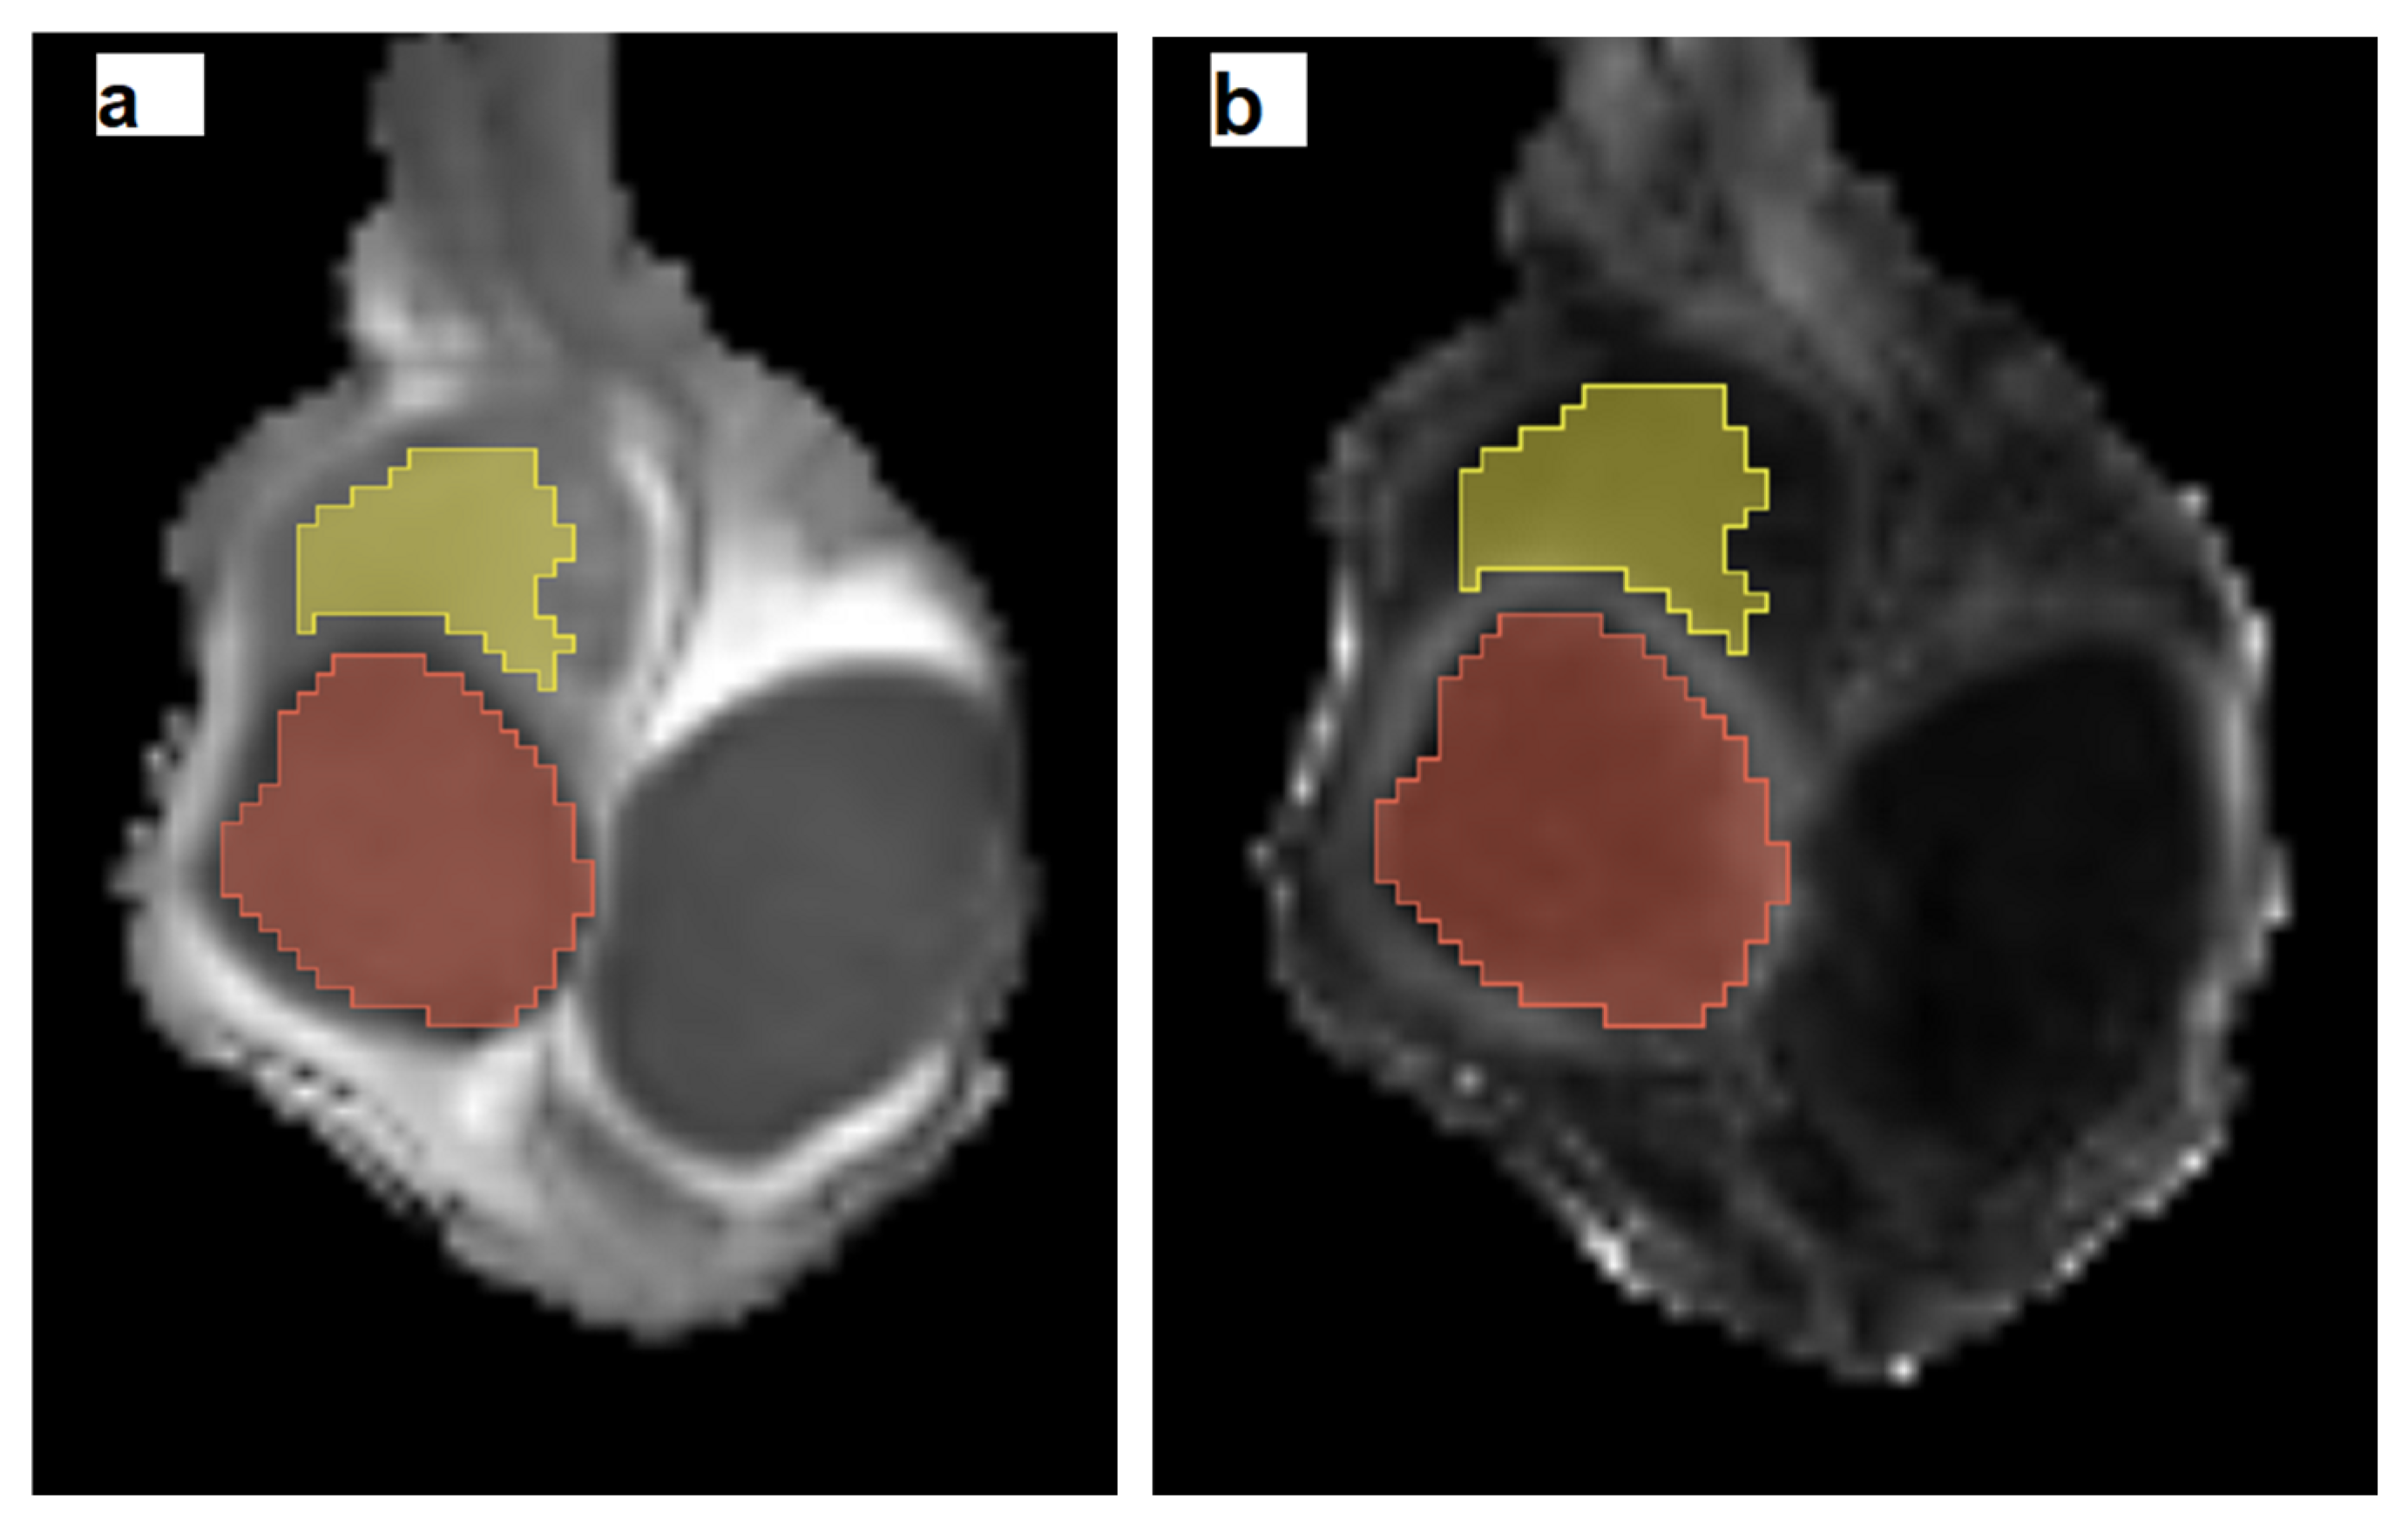

2.3. MRI Data Postprocessing